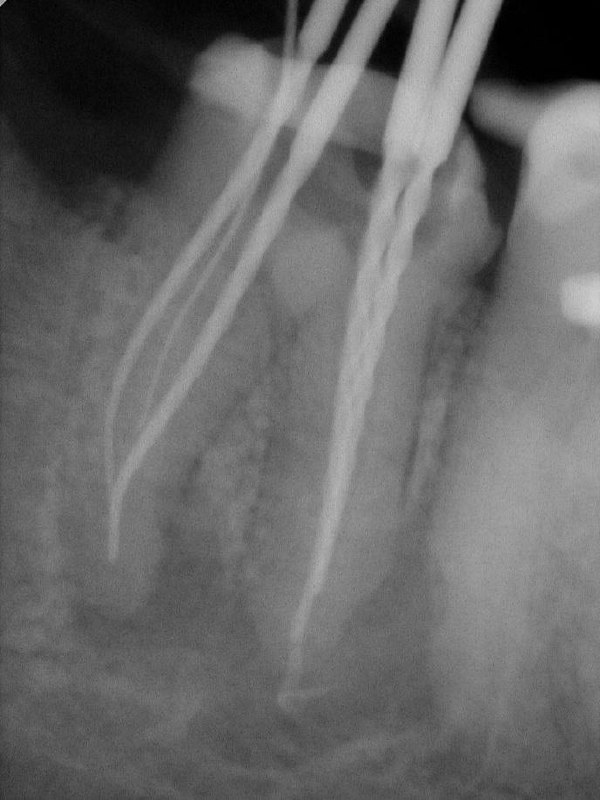

- Два анкерных штифта извлечены ✅

- Срединный мезиальный канал найден ✅

- Гуттаперча за апексом — случилось ❌

И ни крючок, ни дебрайдер не помогли её достать.

Лайфхак от Йоши Тераучи: XP-финишер, обязательно только оригинальный, чуть выводим за апекс, аккуратно работаем, и часть гуттаперчи уходит. Не идеально, но клинически — рабочее решение.